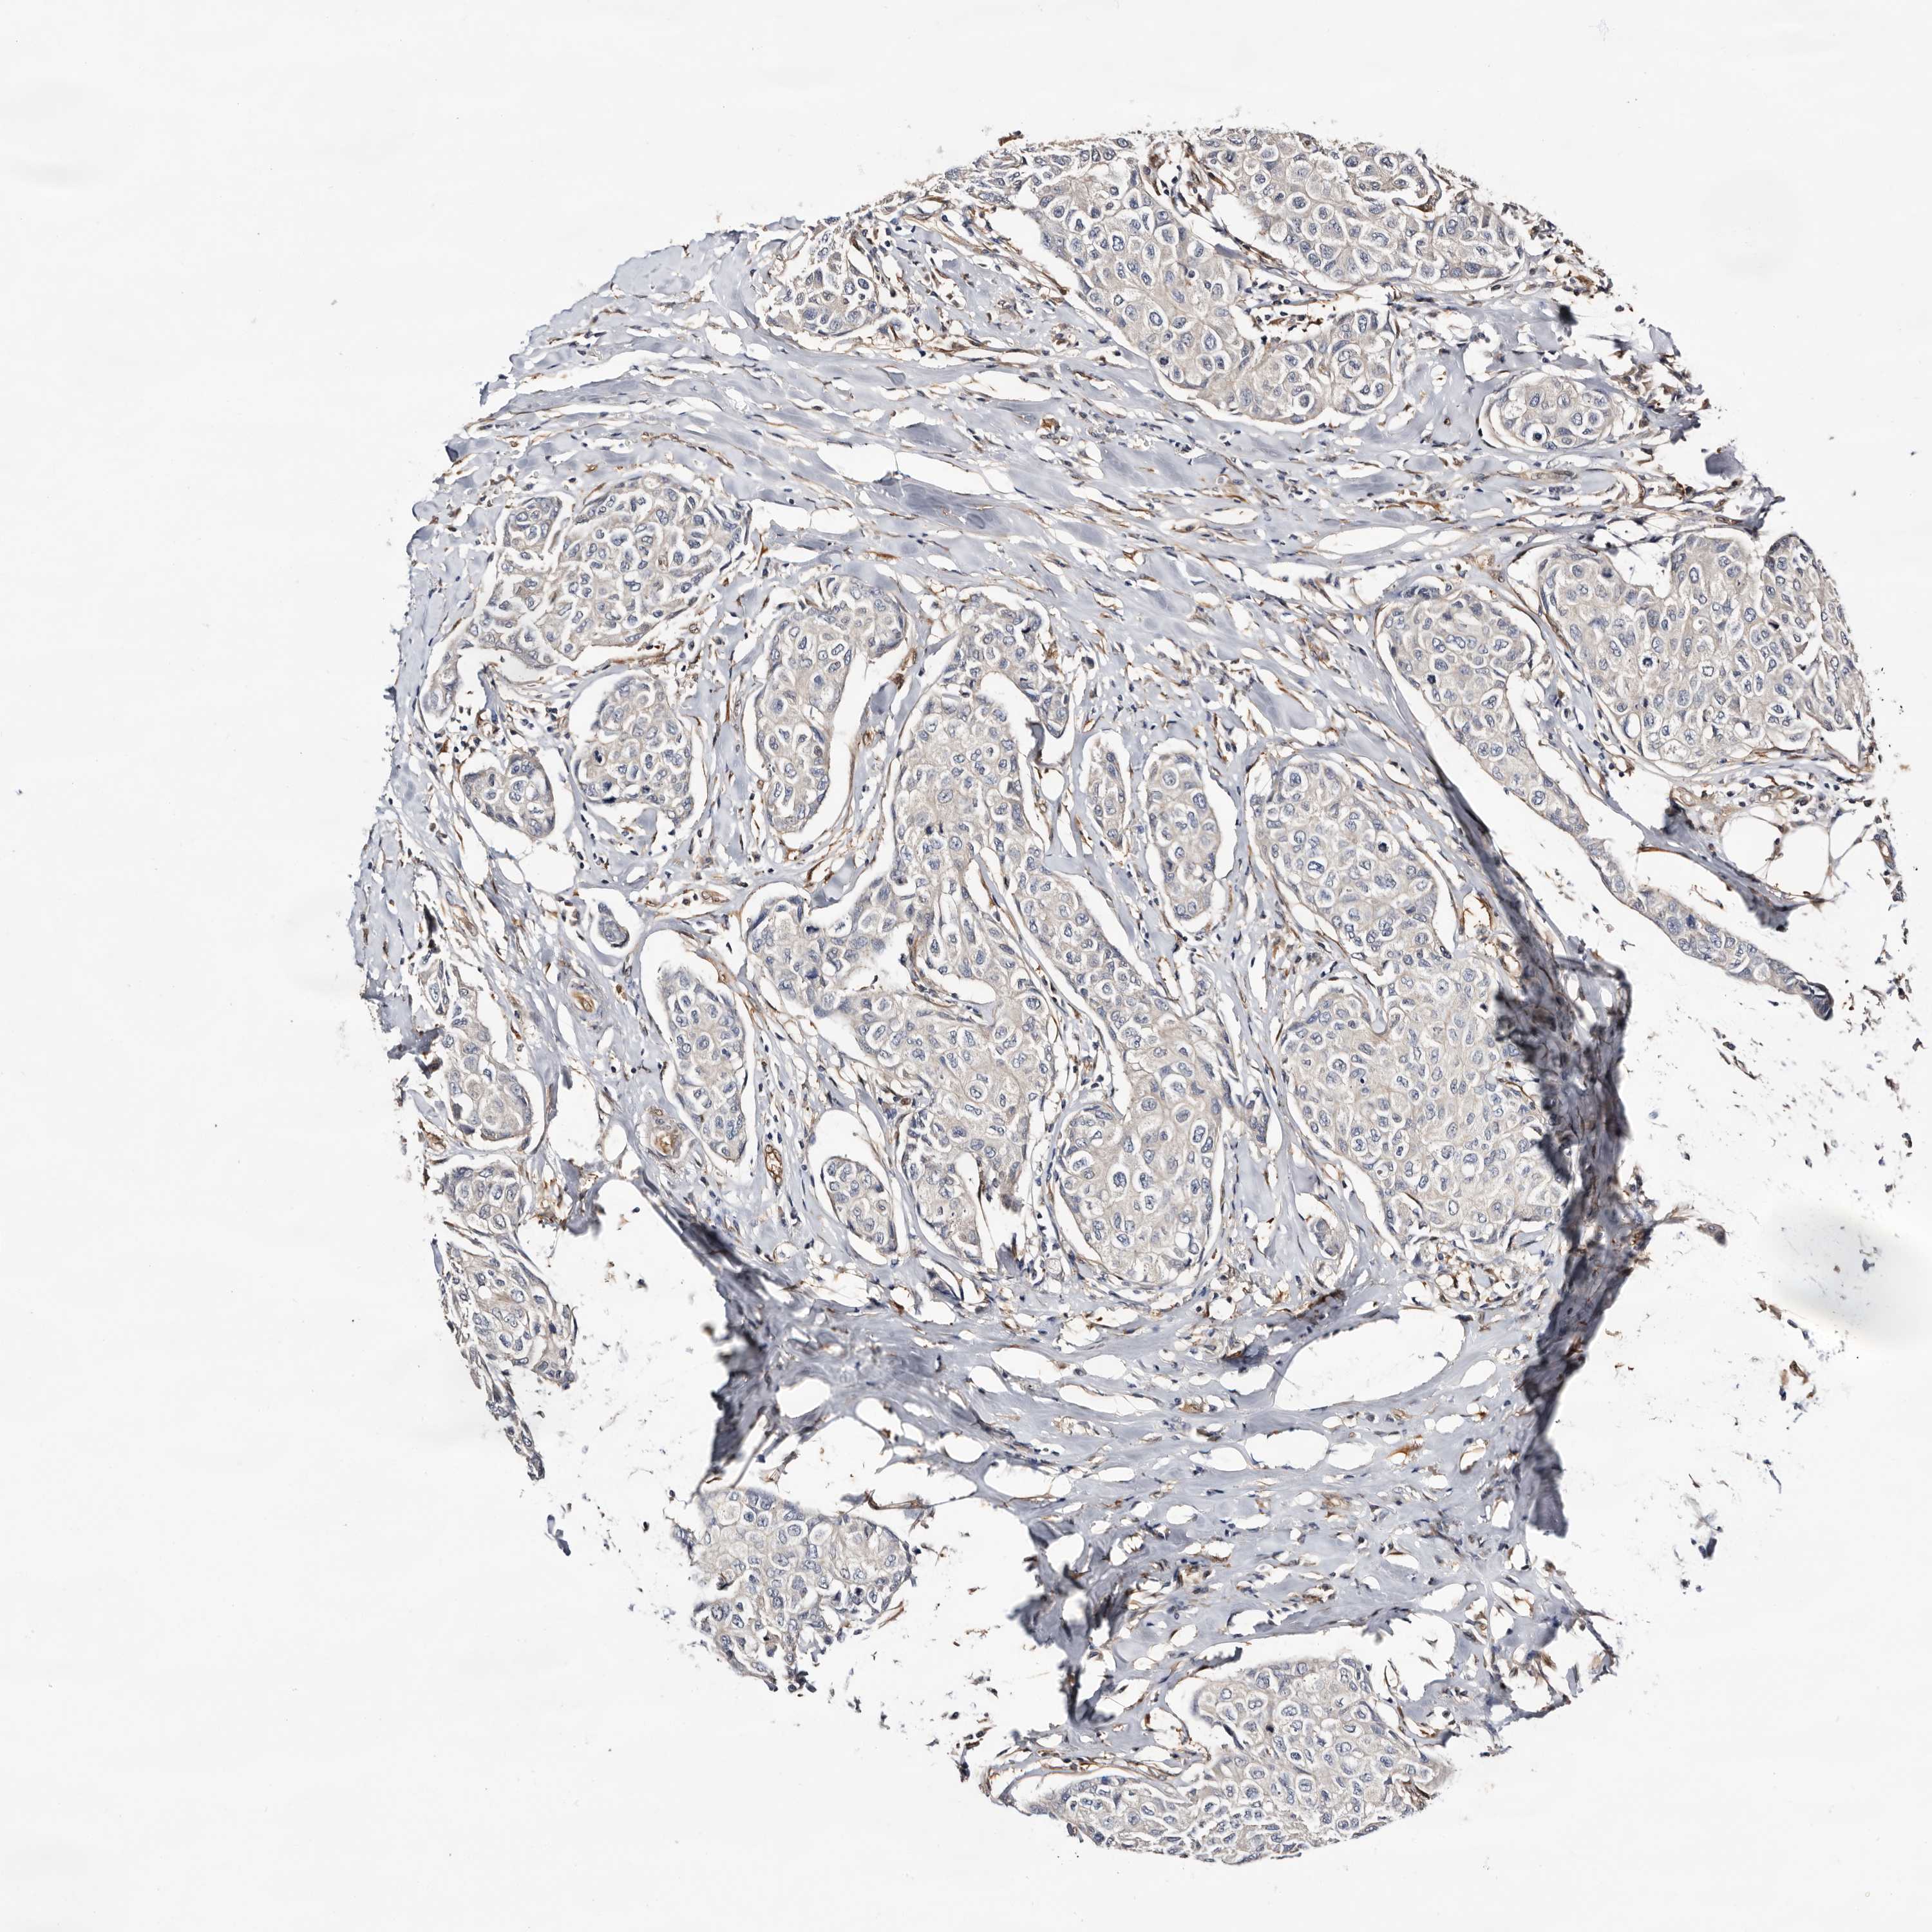

BRCA TCGA BRCA VALIDATION PROTEIN EXPRESSION

ANTIBODIES

AND

VALIDATION